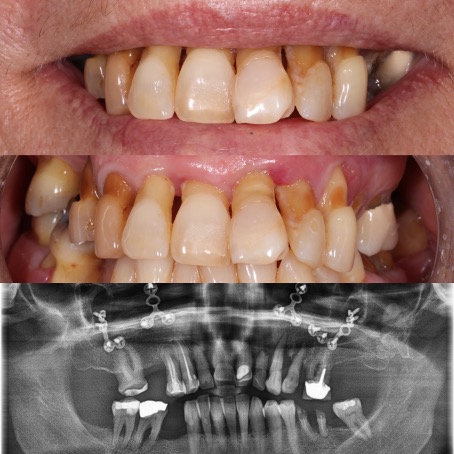

All-on-4®

Édentation totale de la mâchoire – restauration complète fixe avec des implants dentaires

Avant

Après

Selon les techniques modernes de mise en charge immédiate pour les patients édentée, nous avons la possibilité, dans la plupart des cas, d’offrir des dents fixes aux patients dans la journée.

Le protocole All-on-4® permet de réaliser immédiatement une prothèse fixe avec seulement quatre implants par mâchoire. Les implants du fond sont mis en place avec une inclinaison de 30 à 45 degrés, dans les cas où des dents encore présentes devraient être extraites le tout est fait pendant la même opération, la journée se termine pour le patient avec l’installation des dents fixes dans le 90% des cas. Une prothèse définitive sera réalisée environ 4 mois plus tard.

En cas d’atrophie osseuse importante de la mâchoire supérieure, après avoir porté, par exemple pendant des années, une prothèse complète, la masse osseuse a parfois disparu et une implantation normale devient impossible selon les techniques traditionnelles. Dans ce cas une option avantageuse par rapport à une greffe osseuse de grande envergure est le placement d’implants zygomatiques.

Les implants zygomatiques et ptérygoïdiens représentent une alternative intéressante à la greffe osseuse en cas d’atrophie osseuse importante de la mâchoire supérieure édentée. Des implants spéciaux, très longs (env. 50 mm) sont ancrés dans l’os zygomatique et servent de support à un bridge fixe implanto-porté.

Le bridge, fixé par des vis sur les implants, est conçu selon la méthode All-on-4®. En cas d’atrophie osseuse grave du maxillaire, les implants zygomatiques et ptérygoïdiens sont la seule possibilité qui existe pour réaliser une prothèse fixe et immédiate sans avoir recours à une greffe osseuse de grande envergure.